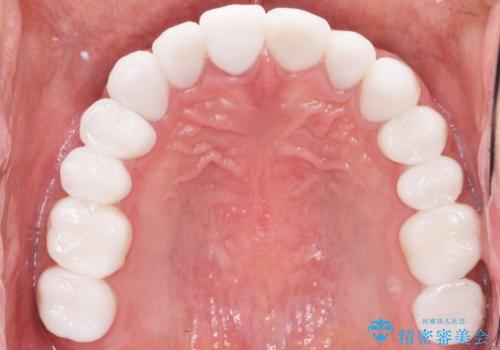

憧れの芸能人のような白い歯に 30代男性

- 憧れの芸能人(ヴィジュアル系バンドマン)のような歯になりたいとのご希望で来院された患者様です。

咬み合わせが悪く矯正も検討されていたそうですが、歯を真っ白にしたいというご希望もあり、28本のすべての歯をセラミックにしたいとのことでした。

精査したところ、ほとんどの歯が保険内のレジンで充填されており、咬み合わせも悪く咬合していない歯もありました。

虫歯をしっかりと治療したのち、オールセラミッククラウンによる補綴治療を行いました。

憧れのヴィジュアル系バンドマンのような白い歯になり、喜んで下さいました。

不適なレジン充填によるデコボコがなくなったことで歯磨きしやすくなり、また気にされていた咬み合わせも良くなり、ご満足頂けました。

クラウンの種類:オールセラミッククラウン スタンダード

シェード:NW0